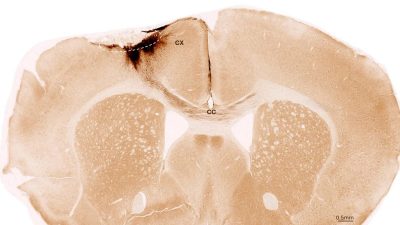

Gli studi hanno utilizzato cellule staminali neurali umane, da cui si possono formare diversi tipi di cellule del sistema nervoso. Le cellule staminali derivavano da cellule staminali pluripotenti indotte, che a loro volta possono essere prodotte da normali cellule somatiche umane. Per la loro ricerca, i ricercatori hanno indotto un ictus permanente nei topi, le cui caratteristiche assomigliano molto alla manifestazione dell’ictus negli esseri umani. Gli animali sono stati geneticamente modificati in modo che non rigettassero le cellule staminali umane.

Una settimana dopo l’induzione dell’ictus, il team di ricerca ha trapiantato cellule staminali neurali nella regione cerebrale lesa e ne ha osservato gli sviluppi successivi utilizzando una varietà di metodi di imaging e biochimici. “Abbiamo scoperto che le cellule staminali sono sopravvissute per l’intero periodo di analisi di cinque settimane e che la maggior parte di esse si è trasformata in neuroni, che in realtà comunicavano persino con le cellule cerebrali già presenti”, afferma Tackenberg.